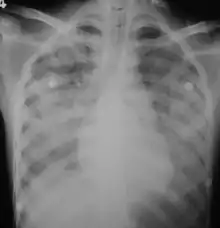

In those who have lung involvement, a chest X-ray may demonstrate diffuse alveolar opacities.[18]